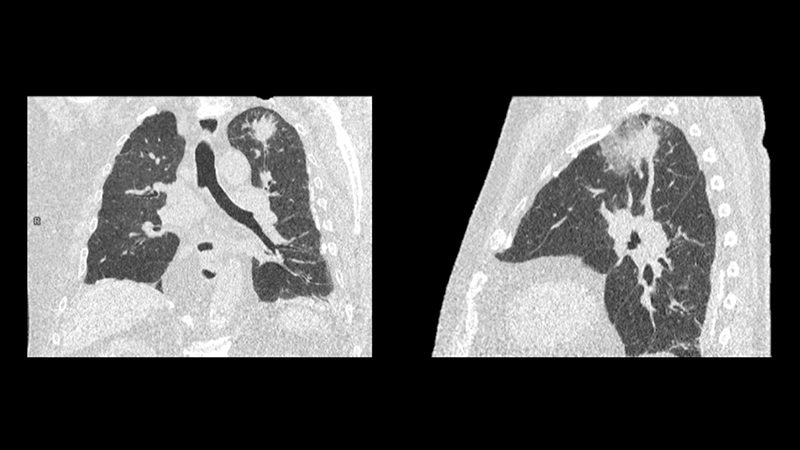

• Aynı anda roleout, koroner arterler ve pulmoner arterler görüntülemesini tek seferde, daha az kimyasal maddeyle renkli görüntülemesini yapabiliyoruz.

• Sanal bronkoskopi ve kolonoskopi yapılması,

Yeni nesil Siemens BT cihazı ile en düşük dozda radyasyonla hızlı tarama yapıyoruz.

Hızlı Tarama